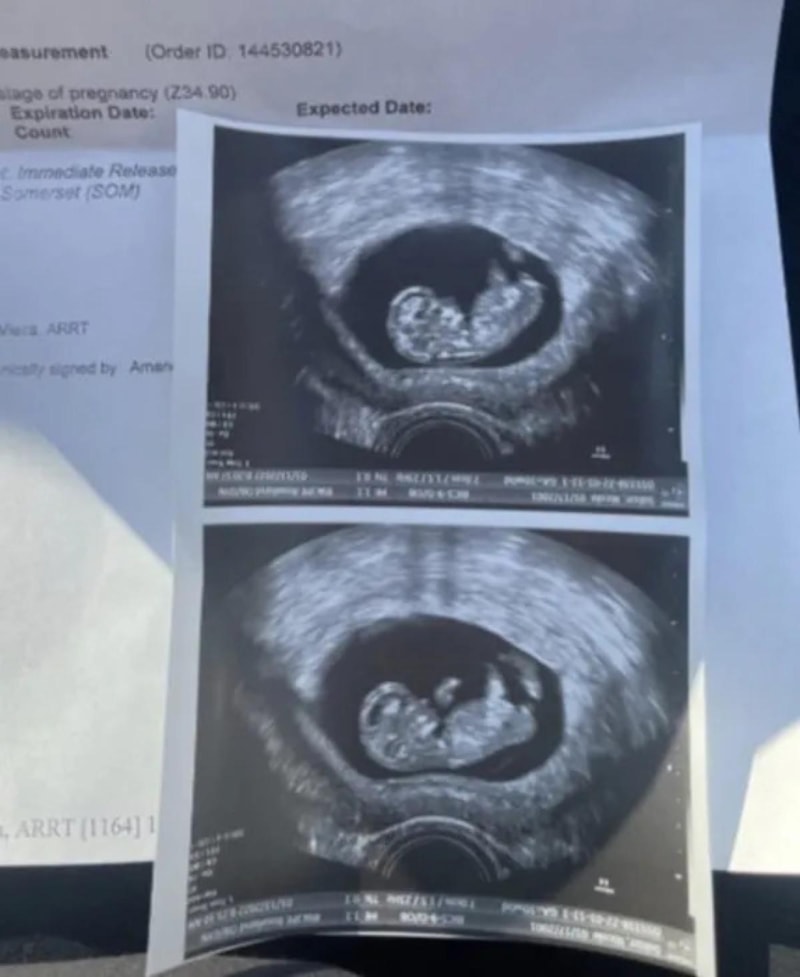

Ancak Nikki Salazar adındaki genç annede bu olağan durum hiç yaşanmadı desek sizlere de inandırıcı gelmez. Hamileliği boyunca karnında herhangi bir şişlik meydana gelmeden dümdüz karınla 9 ayını tamamlayan Salazar görenleri hayrete düşürmeyi başardı.

4 milyon üzerinde izlenmeye ulaşan videosunda Salazar, minik oğlunun doğumuna 12 gün kala bile karnında herhangi bir değişiklik olmamasıyla izleyenleri hayrete düşürdü.

Daha hamileliğin başlangıcında kilo kaybetmeyle başladığı süreçte bebeğin büyüdüğüne dair tüm belirtilerin olmasına rağmen karnında hiçbir şişlik olmaması oldukça ilgi çekiciydi.

Sekiz aya geldiğinde ise çok ağır hissetmeye başlamasına rağmen görünüşte yine de herhangi farklılık olmadığını dile getirdi. Çılgın bir deneyim olarak tanımladığı o döneme baktığında ise genç anne, hastanede bile kimsenin onun bebek taşıdığını anlayamadığını iddia etti.